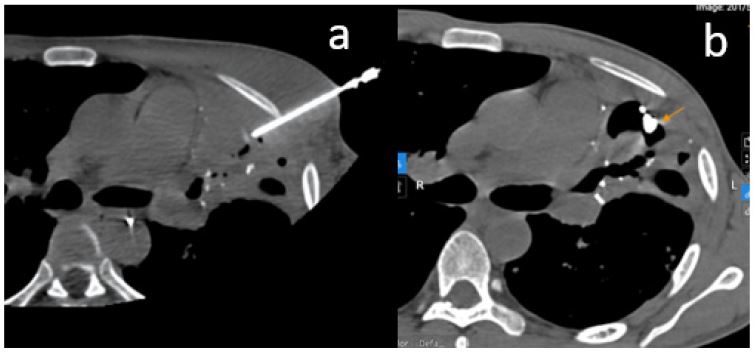

A second intervention was planned. Attempts to access the pseudoaneurysm via the pulmonary artery failed due to the small and peripheral feeding branch. Delayed-phase (7-second) angiography of the left subclavian artery revealed ongoing perfusion of the pseudoaneurysm through a lateral thoracic artery branch. An attempt at direct puncture under DSA guidance with an 18G needle was unsuccessful, and the patient experienced a 50 mL hemoptysis episode, which was managed locally. This confirmed that the pseudoaneurysm still had active blood flow.

Figure 3: (A) Digital Subtraction Angiography (DSA) of the pulmonary artery shows absence of several left pulmonary arterial branches due to increased vascular resistance from underlying pulmonary damage and reversed blood flow. Selective catheterization of the pseudoaneurysm via the pulmonary artery failed due to the small and inaccessible feeding branch. (B) Attempted direct puncture using an 18G needle under DSA guidance was unsuccessful. The patient experienced 50 mL of hemoptysis, which was managed locally, resulting in temporary hemostasis.

In situations where endovascular access fails or is anatomically unfeasible, percutaneous puncture techniques may be considered, although they carry inherent risks such as pneumothorax or pseudoaneurysm rupture if not performed with precision [3,6]. In the reported case, the initial attempt at direct puncture under DSA guidance failed and resulted in a temporary recurrence of hemoptysis. Subsequently, CT-guided intervention allowed for precise localization of the pseudoaneurysm and accurate delivery of glue, achieving definitive therapeutic success. Using a higher NBCA-to-lipiodol ratio (1:2) increased the mixture’s viscosity, limiting glue dispersion and reducing the risk of non-target embolization.